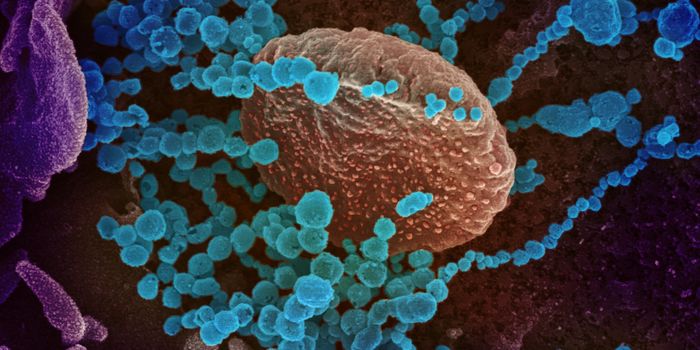

AUG 19, 2020Cell & Molecular BiologyAs the pandemic virus, SARS-CoV-2 continues to cause tens of thousands of new cases of COVID-19 every day in the United ...

APR 27, 2020MicrobiologyThe pandemic virus that causes COVID-19 has now infected nearly 3 million people, and killed over 200,000.

MAY 10, 2021MicrobiologyThe pandemic virus SARS-CoV-2 has changed the world in devastating ways, taking hundreds of thousands of lives & new var ...